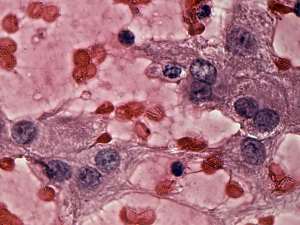

Cytology was performed from one of the moderately hypoechogenic lesions. It was located next lateral to the echonormal lesion. There were two cell populations on the smear: beside regular thyrocytes, follicular cells presenting oxyphilic metaplasia were also found on the smear.

Combined cytological-clinical-sonographic diagnosis: benign lesion presenting oxyphilic metaplasia.

A right lobectomy was performed. Histopathology disclosed benign hyperplastic nodules and chronic lymphocytic thyroiditis.

The possibility of an oxyphilic tumor could not be fully excluded solely on cytology.